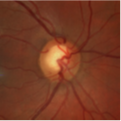

The OCT Exam is a quick, non-invasive scan that allows our doctors to see all 10 layers of your retina. The Clarus retinal camera gives a view into the periphery of your eye normally not accessible without a dilated pupil.

Eye Wellness Exam Examples

Healthy Retina Unhealthy Retina

If you choose not to have your eyes dilated because of the possibility of blur and light sensitivity, our doctors would strongly suggest you to have a wider view photo of the back of your eye.